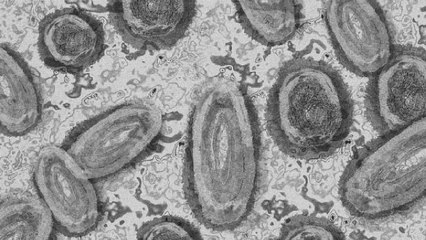

La Secretaría de Salud confirmó el primer caso importado de la #ViruelaDelMono en México.